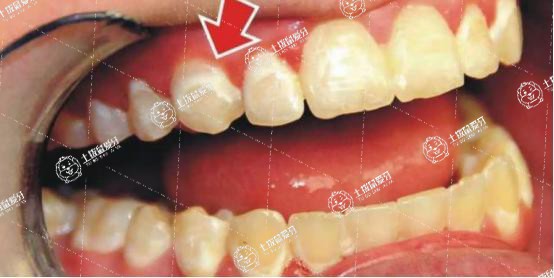

地包天牙齒矯正的最佳年齡和價(jià)格 地包天牙齒矯正過程

在這個(gè)顏值社會(huì),大家對(duì)自己的外貌還是相當(dāng)重視的,很多牙友們?cè)谂R床上因?yàn)樽陨碛懈鞣N牙齒問題顏值大打折扣,尤其是當(dāng)牙友們有地包天的情況的話,及時(shí)做牙齒矯正地包天牙齒矯正的最佳年齡和價(jià)格是什么?對(duì)此,接下來,我們一起來了解一下。

很多小孩子有遺傳方面的原因,或者生長(zhǎng)發(fā)育出現(xiàn)了一定的影響,可能會(huì)導(dǎo)致出現(xiàn)地包天現(xiàn)象,這種情況下,可以通過到正規(guī)的醫(yī)院進(jìn)行矯正,但是還是年齡比較小的情況下,最好不要通過醫(yī)療的方法來矯正,一般地包天這種癥狀矯正的時(shí)候是需要一定的年齡限制,下面就介紹一下矯正地包天的最佳年齡。